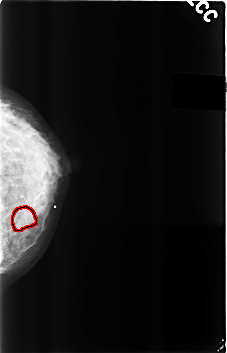

C_0289_1.LEFT_CC

LEFT_CC LINES 4584 PIXELS_PER_LINE 2944 BITS_PER_PIXEL 12 RESOLUTION 50 OVERLAY

FILE: C_0289_1.LEFT_CC.OVERLAY

TOTAL_ABNORMALITIES 1

ABNORMALITY 1

LESION_TYPE MASS SHAPE OVAL MARGINS OBSCURED

ASSESSMENT 4

SUBTLETY 2

PATHOLOGY BENIGN

TOTAL_OUTLINES 1

BOUNDARY